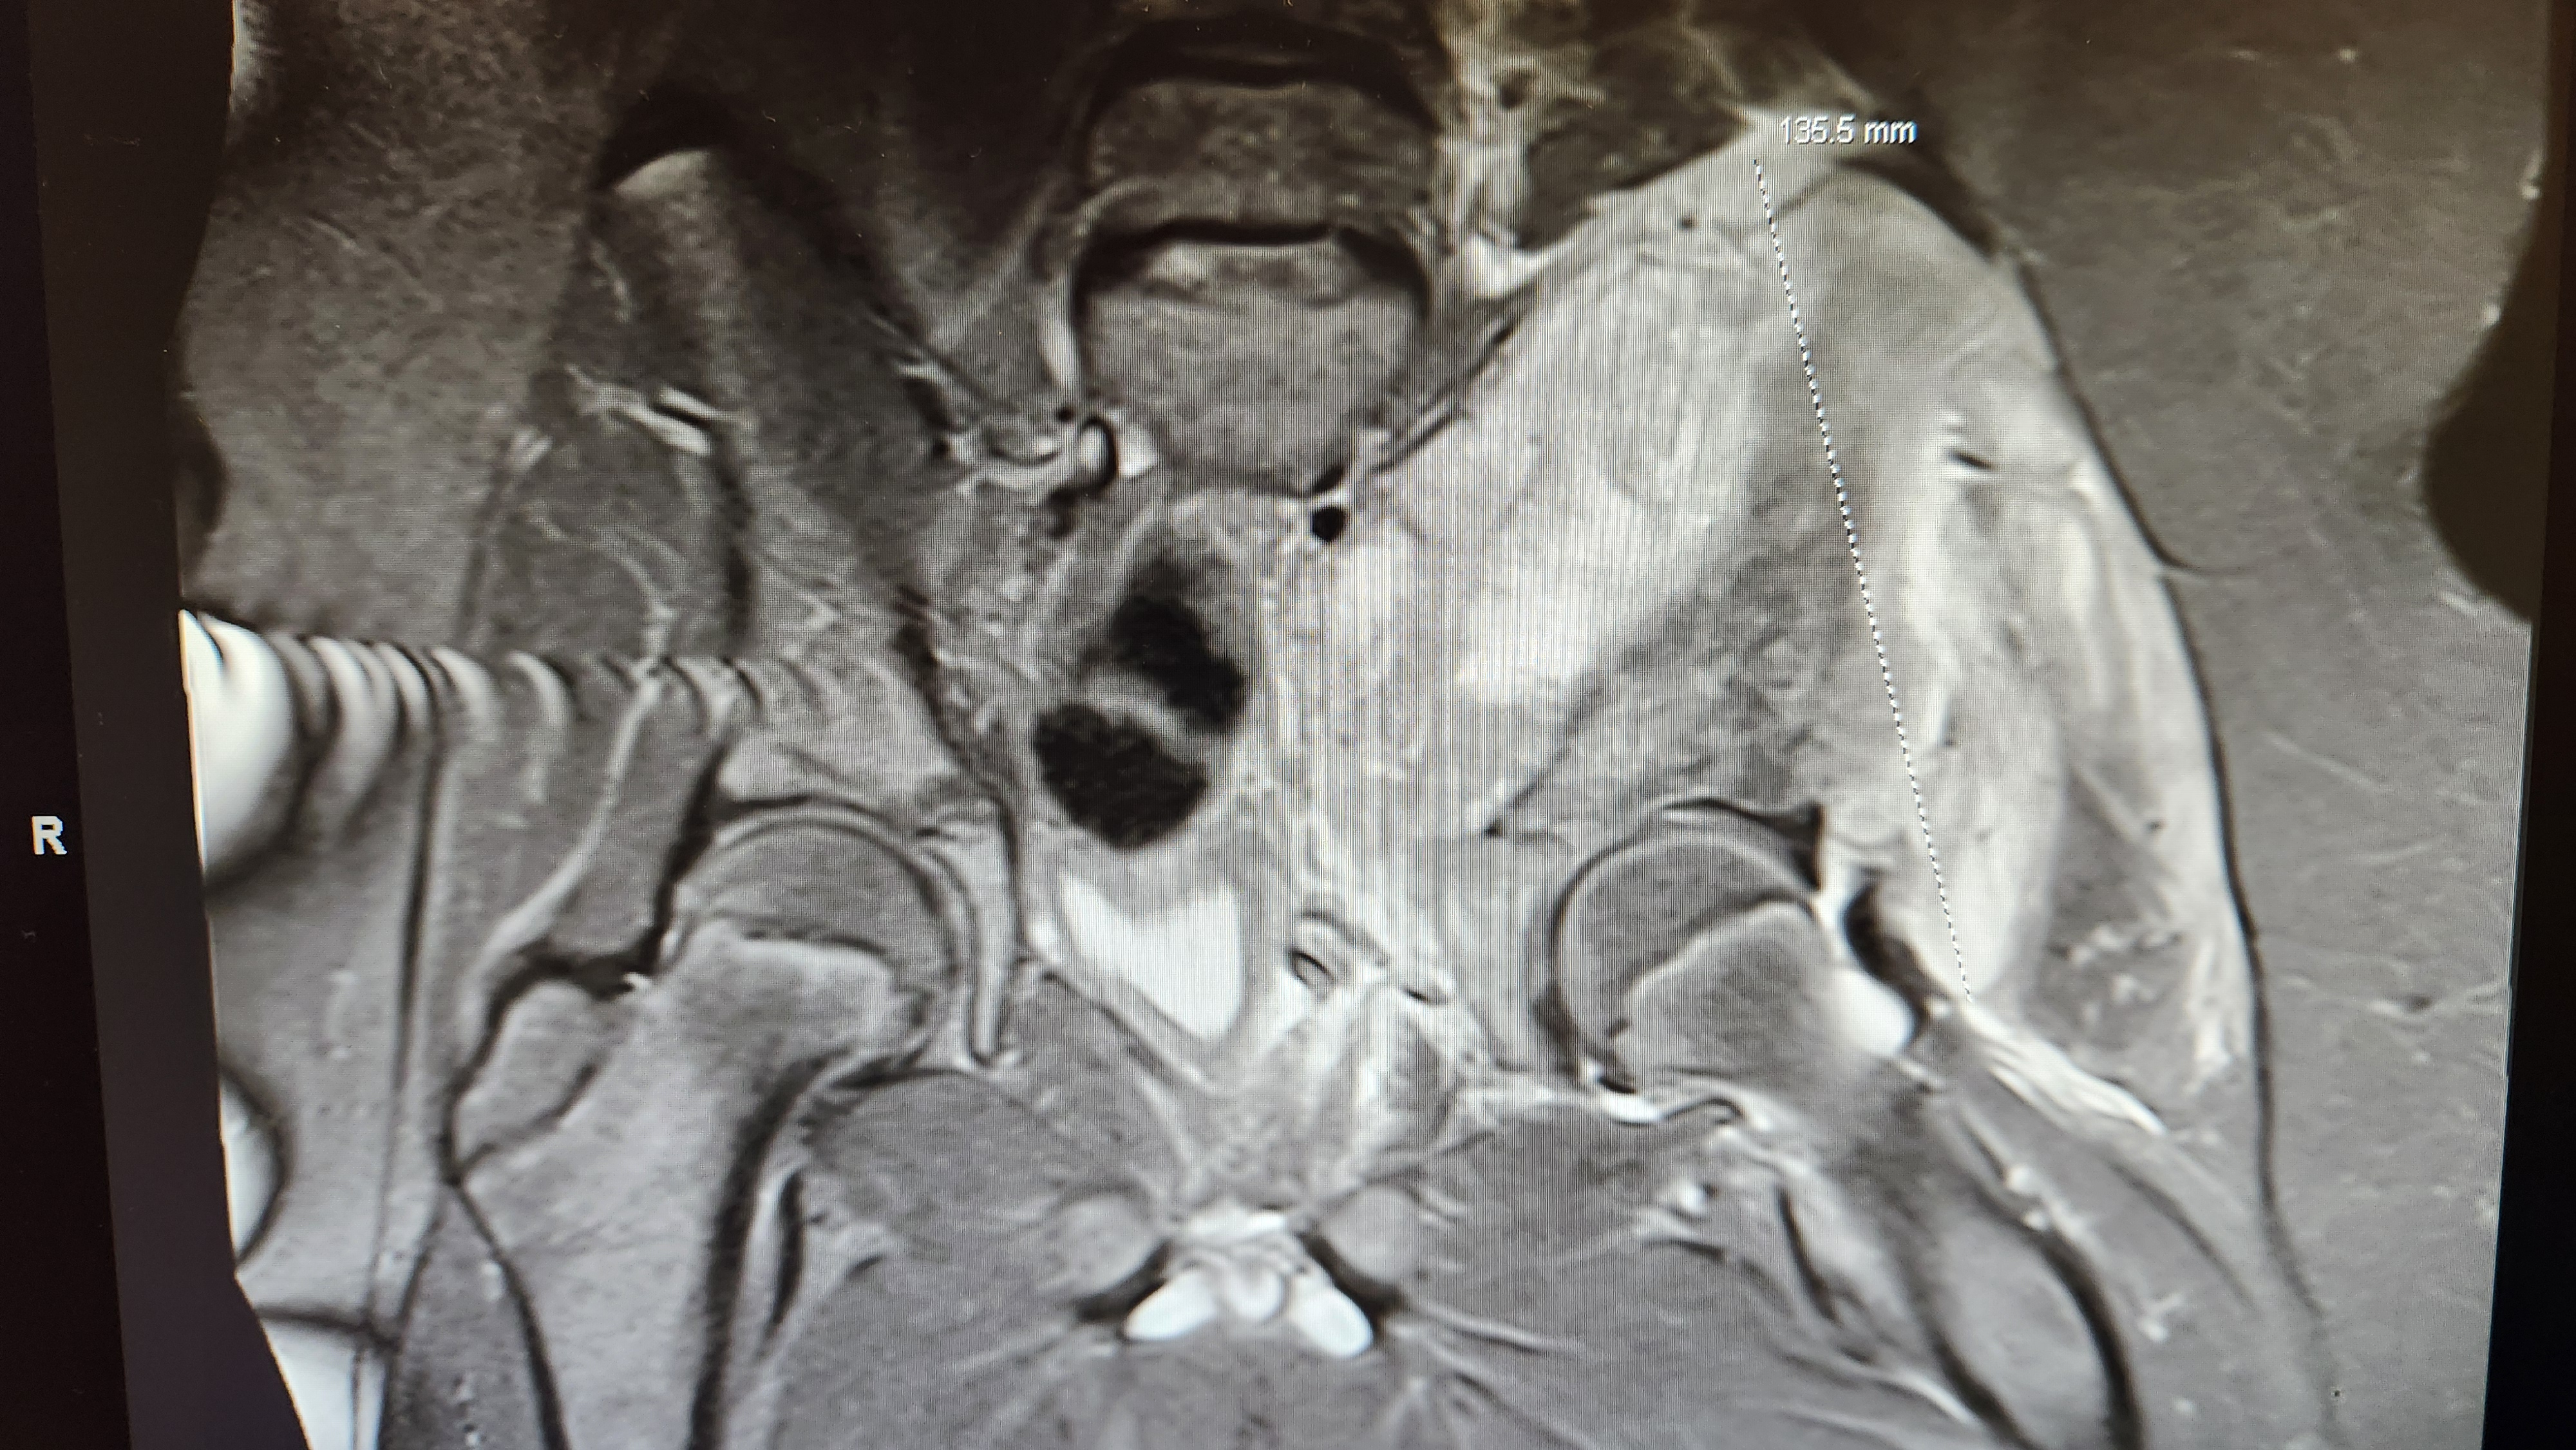

I'm an MRI tech. It's extremely common for patients to not know which part they are getting scanned. Partially because patients are very ignorant but also because often times you go into the magnet completely and just assume it's the whole body getting scanned. In reality MRI is extremely part-specific and time consuming so unless you were in the magnet for two hours you didn't get a whole body scan . Getting one also means fucking nothing. Old people get stroke workups every day because they're fucking old and technically a headache is a symptom of a stroke. Lots of back pain too. Means Jack shit except trump is old and his body is old. Have some terminal pediatric cancer.